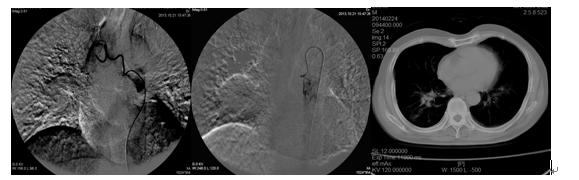

(一)、患者、男、72岁,2013年10月CT +病检提示右肺中心型肺癌,在我院介入诊疗科采用采用支气管动脉造影+化疗栓塞术,术后采用中药调养,一年后复查病灶基本消失。